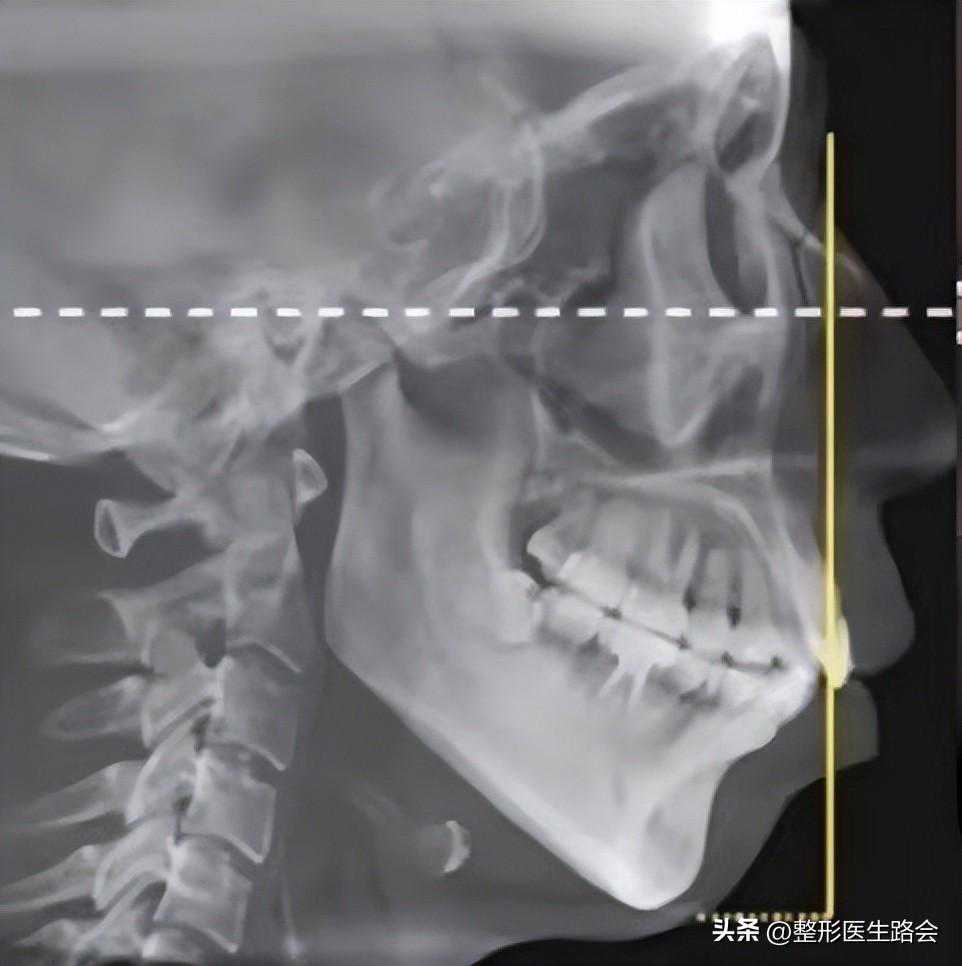

大家问的最多的是骨性嘴凸,顾名思义,其实就是骨骼的问题,牙齿可能是整齐的,但是你承载牙齿的骨骼向前突出或者是发育过度,这个就属于颌面问题,主要就是上颌骨和下颌骨这两方面的问题,那你如何判断是否属于骨性嘴凸呢?其实也不是随便看看你的一张照片就能判定的,必须要拍片,通过专业的投影测量数据才能知道。重点来了啊,骨性嘴凸如何改善?

通常来说,解决骨性嘴凸最高效彻底的方法就是正颌,它通常包括几种具体的情况,比如上颌发育过度,你可以通过上颌骨节骨进行后推改善,下颌发育不足,通过前移下颌或者是颏成型手术来改善.